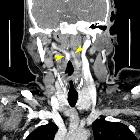

Retropharyngeale

"Kissing Carotids" in der Computertomografie axial, koronar, sagittal und Volumen Rendering. Die elongierten Karotiden treffen sich medial retropharyngeal.

Kissing

carotids: a lovely term for an anatomic variant with great clinical significance. Coronal reconstructed image showing the two internal carotid arteries in close proximity (arrowheads).

carotids: a lovely term for an anatomic variant with great clinical significance. This axial MDCT image shows the level where the two ICA (arrows) are situated in the retropharyngeal space and in close proximity (4mm). The right ICA is more hyperdense than the left due to artefacts.